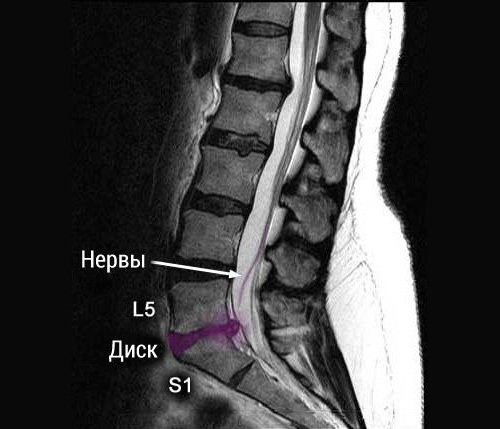

Сверху и снизу каждый позвонок покрыт тонкой хрящевой тканью, благодаря которой и обеспечивается питание межпозвоночного диска. При значительных нагрузках позвоночника ухудшается проникновение питательных компонентов. Из-за этого возникает грыжа диска L5 S1, так как на диски расположенные между этими позвонками приходится самая большая нагрузка.

В этом сегменте выпячивание образуется чаще всего. Нередко грыжа диска l5 S1 распространяется и на близлежащие зоны. Рассматриваемая патология свидетельствует о том, что выпячивание пульпозного ядра произошло (если это начальный этап) между пятым поясничным и первым крестцовыми элементами. Именно в данной области отмечается наибольшая нагрузка на позвоночный столб в процессе движения человека. Грыжа диска l5 S1 может являться следствием травмирования или перенесенных заболеваний. При постоянных физических перенапряжениях ситуация ухудшается.

Грыжа диска L5 S1

Грыжа диска L5 S1 образуется в поясничном отделе и в этом процессе задействованы самые нижние позвонки. Эта патология проявляется из-за анатомических особенностей, так как на поясницу оказывается чрезмерное давление. Болезнь локализуется именно в пояснично-крестцовом отделе позвоночного столба. Эта область считается наиболее подвижной.

- Магнитно–резонансная томография. Она показывает наличие отечности тканей, дает биохимическую информацию о выпячивании, степени развития патологии, ее фрагментации.